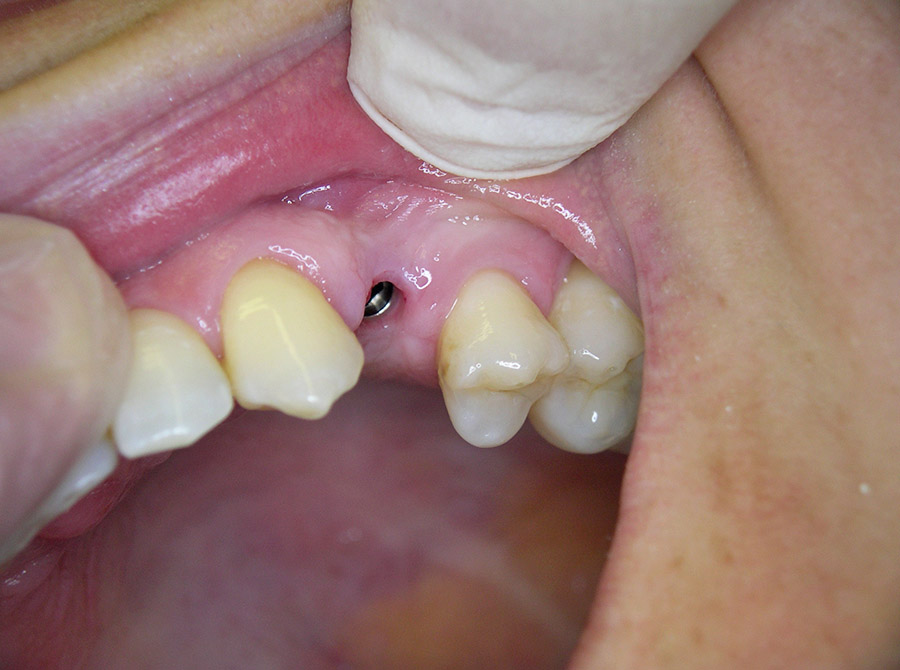

Ein besonderer positiver Effekt der Implantate ist, dass sie den Kieferknochen und das Zahnfleisch erhalten, während sich der Knochen unter Brücken und Prothesen hingegen abbaut. In vielen Fällen lässt sich so die natürliche Rot-Weiß-Ästhetik, also das harmonische Zusammenspiel von Zahnfleisch und Zähnen erhalten, so dass implantat-getragene Kronen kaum von eigenen gesunden Zähnen zu unterscheiden sind.

So können Lücken geschlossen werden, ohne dass gesunde Nachbarzähne beschliffen werden müssen und unnötig Zahnsubstanz abgetragen wird (Brückenversorgung).